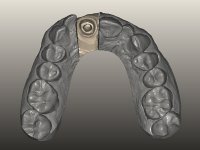

The endocrown should be constructed with a zirconia framework with an ‘intra-root’ and crown components, being this last one veneered with ceramics.

CAD-CAM technology was used to design and construct an endocrown with a zirconia framework veneered with ceramics. The crown was then bonded to the tooth, by using an MDP based adhesive and a dual polymerization composite resin.